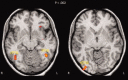

Statistical regularities pervade our perceptual world. Assuming that the human brain is tuned for satisfying the constraints of the visual environment, visual system computations should be optimized for processing such regularities. A socially relevant and highly recurrent homogenous pattern for which the brain has developed sensitivity is certainly the human face. Yet, for which statistical regularities the face sensitive regions are tuned for, and to what extent their detection occurs automatically is largely unexplored. Using fMRI we measured activations within the face sensitive areas for nonface symmetrical and asymmetrical curvilinear patterns with either more high-contrast elements in the upper or in the lower part. Faceness evaluation performed outside of the scanner showed that these patterns were not perceived as schematic faces. Noticeably, symmetry violations disrupted perception of faceness, despite objective image similarity measures showing high faceness values for those patterns. Among the faces sensitive regions, only the right Fusiform Face Area (FFA) showed sensitivity to symmetry. This region showed also greater responses to patterns with more elements in the upper part. Critically, the FFA's responses were more strongly correlated with the physical objective faceness properties of the stimuli than the perceived subjective faceness ratings of the observers. These findings provide direct evidence that the neural computations of the right FFA are tuned to curvilinear symmetrical patterns with high-contrasted elements in the upper part, which fit best with the physical structure of human faces. Such low-level geometrical regularities might be used by the FFA to automatically categorize visual shapes as faces.